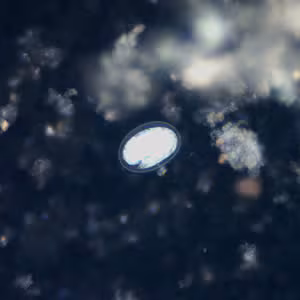

Hookworm eggs.

Microscopic identification of eggs in the stool is the most common method for diagnosing hookworm infection. The recommended procedure is as follows:

- Examine a wet mount of the sediment.

Where concentration procedures are not available, a direct wet mount examination of the specimen is adequate for detecting moderate to heavy infections. For quantitative assessments of infection, various methods such as the Kato-Katz, FLOTAC and Mini-FLOTAC may be used.